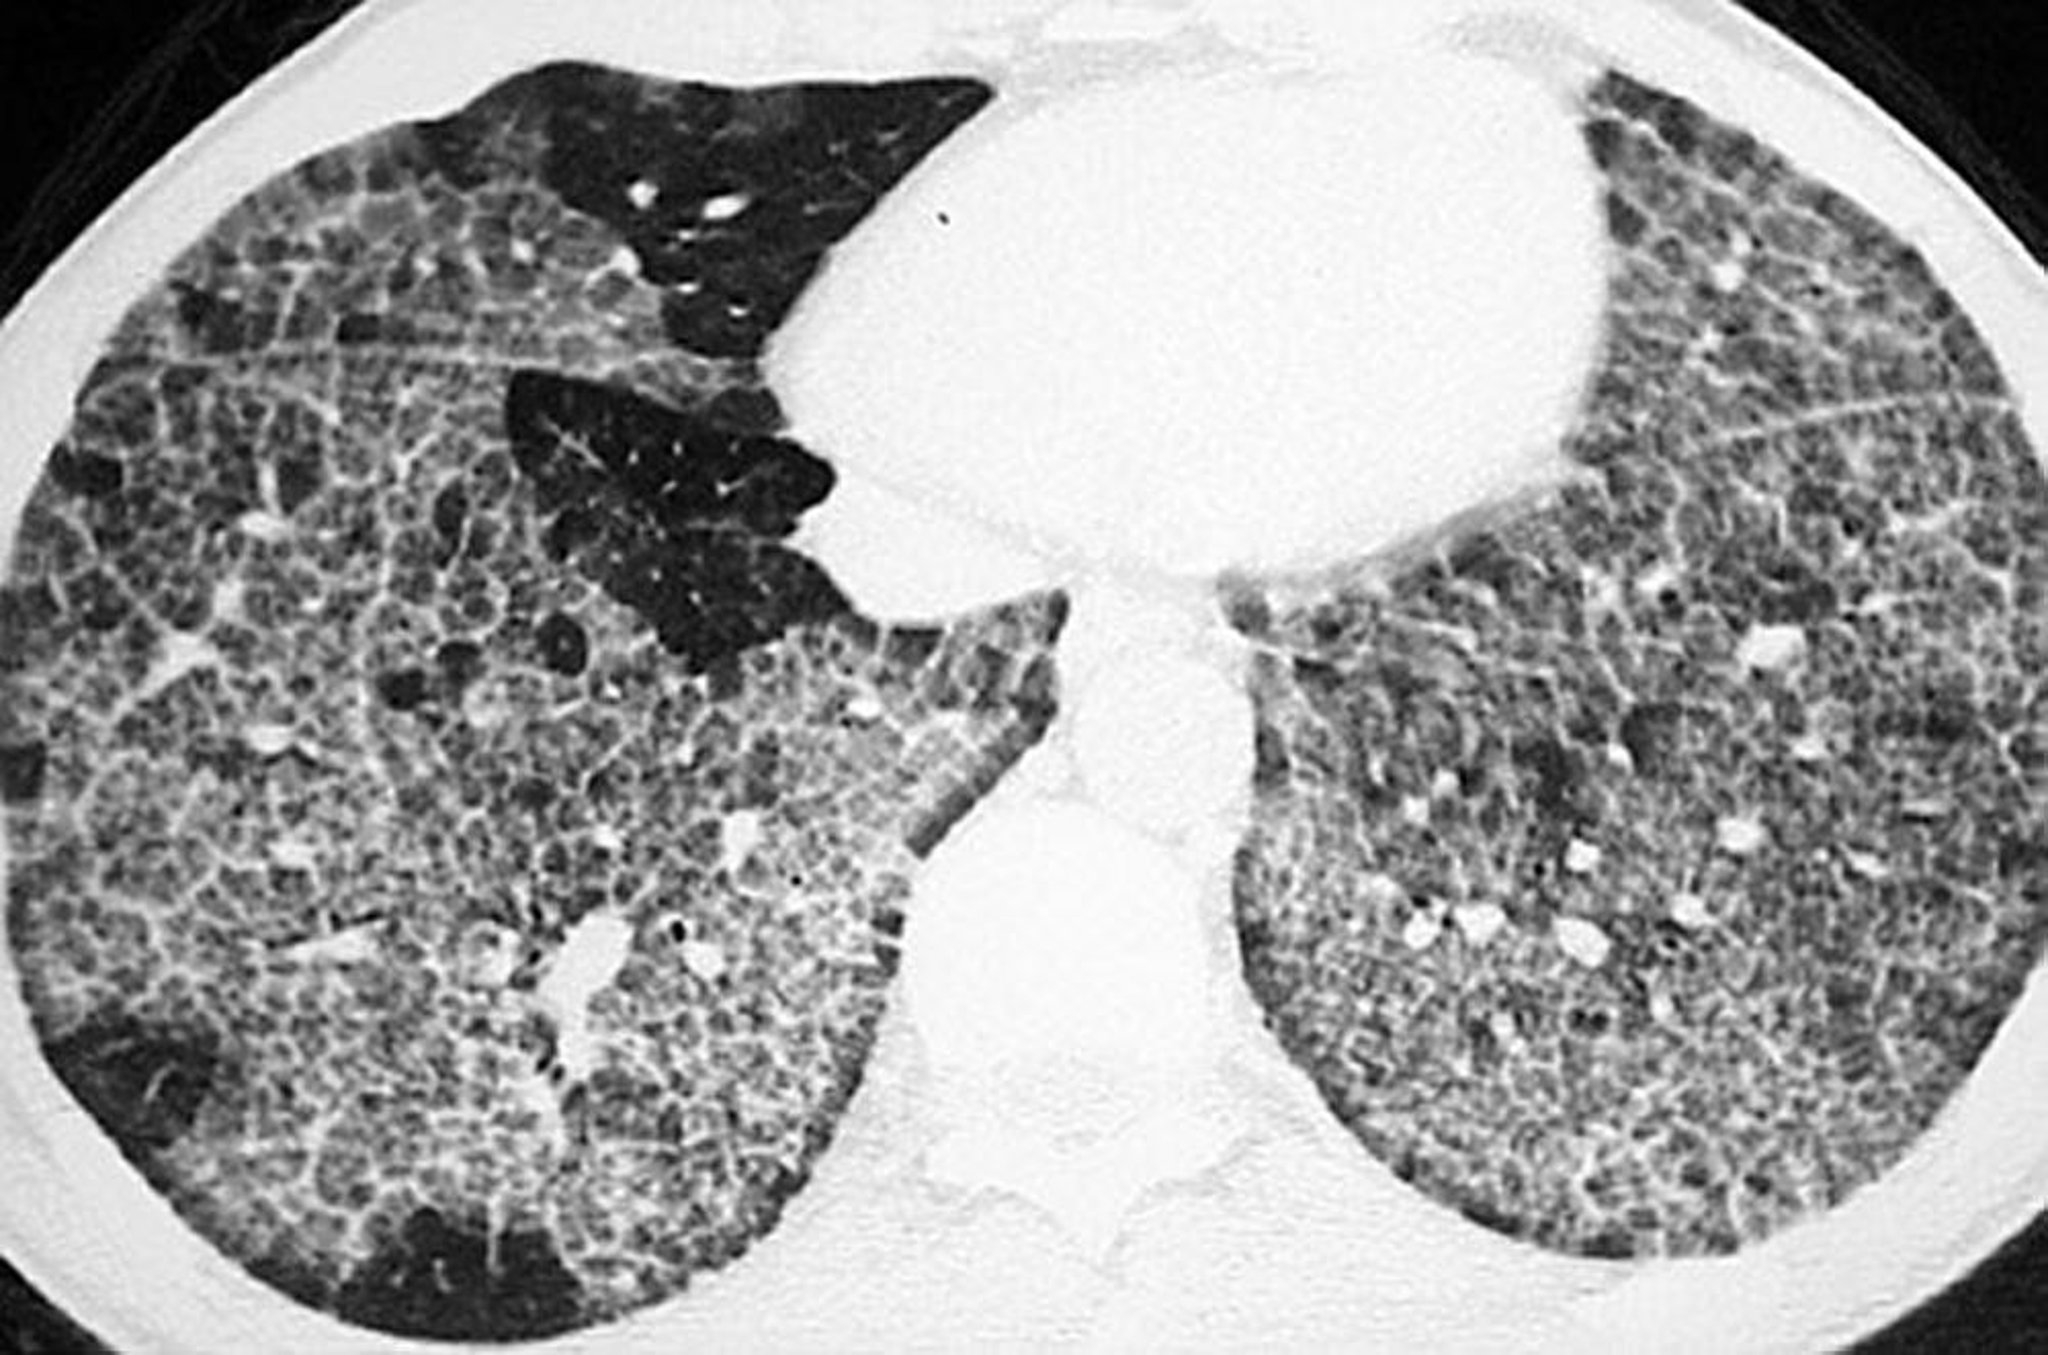

Proteinose alveolar pulmonar (TC)

TC de alta resolução mostra opacificação em vidro fosco e espessamento das estruturas interlobulares e septos em formatos poligonais (“pavimentação em mosaico”).

Imagem cedida por cortesia de Talmadge E. King, MD.